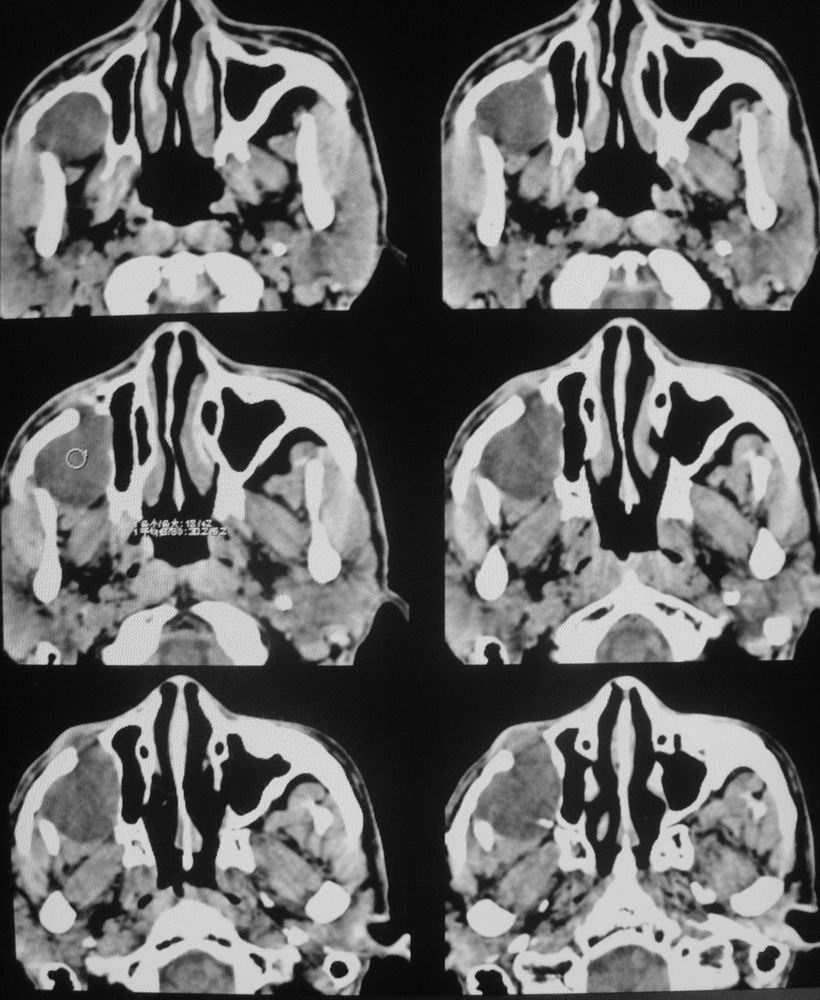

以下是引用zsl6918在2008-5-6 14:41:00的发言:[br]右侧颞下窝内囊性占位(增强未见强化),同侧上颌窦受压变形移位,提示慢性过程。右侧上颌骨局限性吸收破坏,提示良性病变。

以下是引用xuhuihong在2008-5-6 14:57:00的发言:[br]右侧颞下窝内囊性占位(增强未见强化),同侧上颌窦受压变形移位骨质吸收变薄,提示慢性过程。右侧上颌骨局限性吸收破坏,提示良性病变。考虑神经源性肿瘤可能,期待结果。